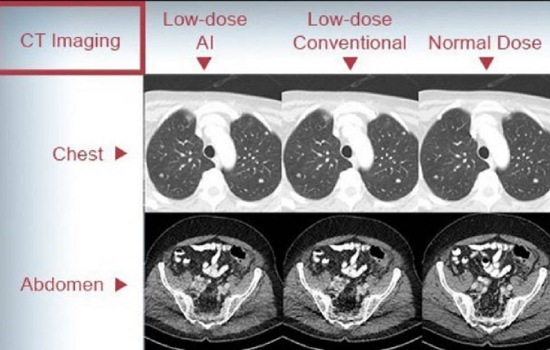

รศ.นพ.ศิระ เลาหทัย แพทย์ผู้เชี่ยวชาญศัลยศาสตร์ ทรวงอกเฉพาะทางด้านการผ่าตัดส่องกล้องในช่องทรวงอก โรงพยาบาลวชิรพยาบาล กล่าวว่า สำหรับโรคมะเร็งปอดยังคงเป็นสาเหตุหลักที่ทำให้เกิดการเสียชีวิตในประเทศไทย จากวารสารทางการแพทย์ได้พบเจอว่า มีผู้ป่วยชาวเอเชียที่ไม่สูบบุหรี่เป็นมะเร็งปอด สัดส่วนถึง 30-60 เปอร์เซ็นต์ โดยแนวทางคัดกรองผู้ที่ไม่สูบบุหรี่เป็นประเด็นที่ซับซ้อน เพราะปัจจุบันมุ่งเน้นไปที่กลุ่มเสี่ยงสูง ซึ่งส่วนใหญ่เป็นผู้ที่สูบบุหรี่หรือเคยสูบหนักมาก่อน ยกตัวอย่าง จากคณะทำงานบริการป้องกันของสหรัฐอเมริกา (USPSTF) แนะนำให้ทำเอกซเรย์คอมพิวเตอร์แบบความเข้มต่ำ (Low-Dose CT หรือ LDCT) ปีละครั้ง สำหรับกลุ่มเสี่ยงสูง 3 ข้อ ประกอบด้วย 1.ผู้มีอายุระหว่าง 50 ถึง 80 ปี 2. มีประวัติการสูบบุหรี่กว่า 20 ปี (เช่น สูบวันละ 1 ซอง เป็นเวลา 20 ปี) และ 3.ยังสูบบุหรี่อยู่หรือเลิกสูบมาไม่เกิน 15 ปี ทั้งนี้ไม่รวมผู้ไม่เคยสูบบุหรี่ แม้ว่าจะมีปัจจัยเสี่ยงอื่นตามมะเร็งปอดไม่รวมผู้ที่ไม่เคยสูบบุหรี่ แม้ว่าจะมีปัจจัยเสี่ยงอื่นก็ตาม

ในส่วนของมะเร็งปอดในกลุ่มผู้ไม่สูบบุหรี่นั้น จากข้อมูลที่ควรรู้ประมาณ 40-60 % ของมะเร็งปอดเกิดในผู้ที่ไม่เคยสูบบุหรี่ซึ่งมักเกิดจากการได้รับควันบุหรี่มือสอง, การสัมผัสก๊าซเรดอน, การสัมผัสสารพิษจากงานอาชีพ (เช่น แร่ใยหิน ควันดีเซล), มลพิษทางอากาศ หรือ ครัวเรือน, ประวัติครอบครัวเป็นมะเร็งปอด, การกลายพันธุ์ทางพันธุกรรม (เช่น EGFR, ALK) โดยมะเร็งปอดในผู้ไม่สูบบุหรี่มักเป็นชนิด อะดีโนคาร์ซิโนมา (Adenocarcinoma) ซึ่งมากกว่า 60-70% มักถูกวินิจฉัยในระยะที่ลุกลามแล้ว เพราะไม่มีการตรวจคัดกรองที่เหมาะสมโดยปัจจุบันยังไม่มีแนวทางการตรวจคัดกรองสำหรับผู้ไม่สูบบุหรี่ระดับชาติหรือสากล ที่ แนะนำให้ตรวจ LDCT เป็นการตรวจเอกซเรย์คอมพิวเตอร์บริเวณทรวงอกด้วยปริมาณรังสีที่ต่ำมาก ใช้เพื่อคัดกรองมะเร็งปอดในระยะเริ่มต้นในผู้ที่ไม่เคยสูบบุหรี่ทั่วไป โดยผลจากการตรวจ LDCT พบว่า 1. อัตราความเสี่ยงต่อประโยชน์ยังไม่ชัดเจน (ตรวจพบผลลวงบ่อย, ได้รับรังสี) และ 2.ยังไม่มีหลักฐานชัดเจนว่าช่วยให้รอดชีวิตเพิ่มขึ้นในกลุ่มความเสี่ยงต่ำ

ส่วนข้อควรระวังและประเมินก่อนตรวจ LDCT นั้น แม้จะช่วยลดอัตราการเสียชีวิตจากมะเร็งปอดในกลุ่มเสี่ยงสูง แต่ก็มีข้อควรพิจารณา เช่น 1. ผลบวกลวง (False Positive) โดยอาจพบก้อนที่ไม่ใช่มะเร็ง ทำให้ต้องตรวจเพิ่มเติมหรือผ่าตัดโดยไม่จำเป็น 2.การได้รับรังสีซ้ำซ้อนและ 3.ความวิตกกังวลจากผลตรวจ โดยมีบางรายอาจมีข้อยกเว้นหรือกรณีพิเศษ อาจมีประโยชน์ต่อการคัดกรองความเสี่ยง ได้แก่ 1.ประวัติครอบครัวที่ชัดเจนว่าเคยเป็นมะเร็งปอด 2.การสัมผัสสารพิษจากสิ่งแวดล้อมหรือจากอาชีพอย่างมีนัยสำคัญและ 3.พันธุกรรมที่เสี่ยงต่อการเป็นมะเร็ง กรณีเหล่านี้ควรพูดคุยกับแพทย์ และพิจารณาอย่างรอบคอบร่วมกัน โดยมากจะอยู่ในบริบทของการวิจัยหรือติดตามเฝ้าระวังกลุ่มเสี่ยงสูง โดยปัจจุบันการใช้ฟิล์มเอกซเรย์ในการตรวจคัดกรองมะเร็งปอดหรือการเจาะเลือด ยังไม่ใช่วิธีมาตรฐานที่มีความแม่นยำอีกต่อไป ฉะนั้นใครที่มีความเสี่ยง อย่าลืมไปคัดกรองมะเร็งปอดโดยการทำ LDCT กันนะครับ